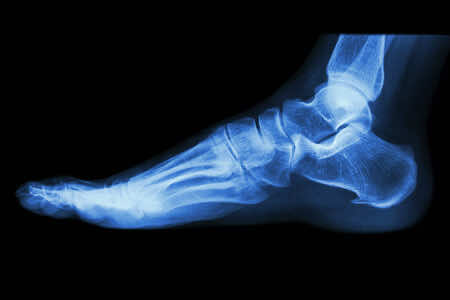

If you have had the symptoms described above for more than a few weeks, it might be time to visit your GP surgery. A GP will examine your feet, observe you walking, and ask questions about your pain, your daily activities and previous injuries and illnesses. Usually this is enough for diagnosis, however they may wish to take an X-ray to rule out a fracture.

A foot X-ray may be recommended to rule out the possibility of a fractured calcaneus causing the pain